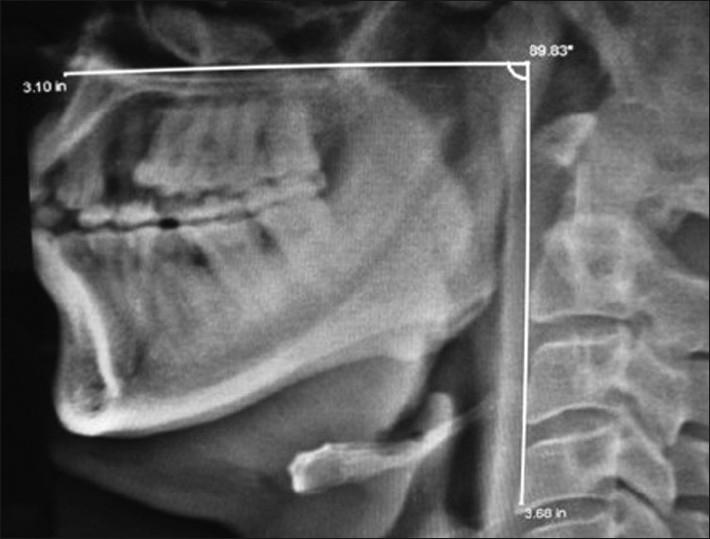

Difficult airway continued to be a major cause of anesthesia-related morbidity and mortality. Successful airway management depends on direct laryngoscopy and tracheal intubation. Difficult laryngoscopy is a resultant of incomplete structural arrangements during the process of head positioning. Through clinical history, examination of the patients along with craniofacial indices alerts the anesthetist for difficult laryngoscopy. But it does not predict all causes of difficult laryngoscopy during pre-anesthetic evaluation. The maxillo-pharyngeal angle, an upper airway anatomical balance, was proposed for better understanding the pathophysiology of difficult laryngoscopy. In our study we have assess difficult laryngoscopy by electronically measuring maxillo-pharyngeal angles on a lateral cervical radiograph. This angle is normally greater than 100°. Less than 90° angle suggests either impossible or difficult direct laryngoscopy when all known craniofacial indices were within the normal range. Cervical radiographic assessment is a simple, economical, and non-invasive predictive method for difficult laryngoscopy. It should be used routinely along with other indices as pre-anesthetic airway assessment criteria to predict the difficult laryngoscopy.

In 148 patients (94.28%), the maxillo-pharyngeal angle was more than 100°, in 7 patients (4.45%) it was less than 90°, and in 2 patients (1.27%) the M-P angle was less than 85° with normal craniofacial indices. When the MP angle was less than 90°, the direct laryngoscopy was difficult which could be compared with to Cormack and Lehane classification grade III and IV.

148例患者(94.28%)的上颌 - 咽角大于100°,7例患者(4.45%)小于90°,2例患者(1.27%)的M - P角小于85°且颅面指数正常。当MP角小于90°时,直接喉镜检查困难,可与Cormack和Lehane分级III级和IV级相比较。